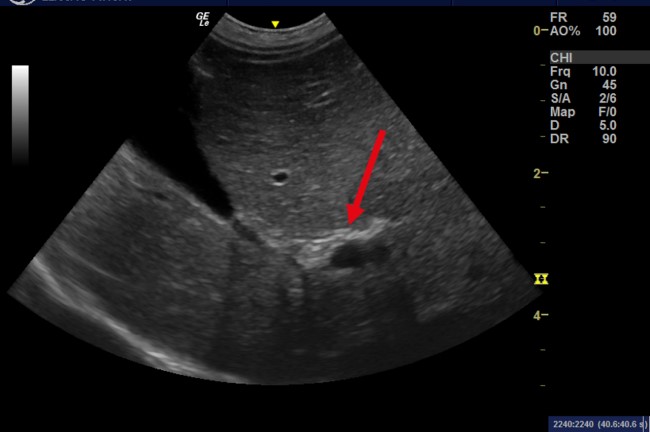

Hình ảnh siêu âm trên gan mèo cho thấy giãn ống mật do sỏi kích thước lớn

Chất khoáng tăng âm trong lòng cổ túi mật và ống mật chủ (mũi tên đỏ). Phía xa trường siêu âm có xuất hiện các dải bóng âm